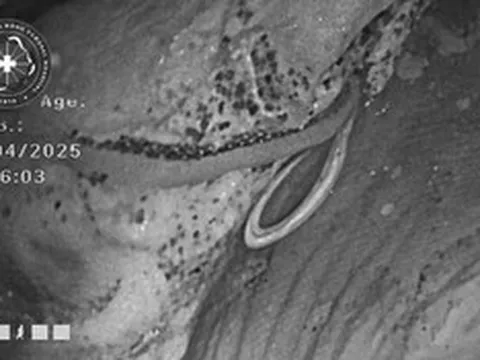

Người đàn ông 62 tuổi tử vong vì suy thận giai đoạn cuối. Ảnh minh họa.